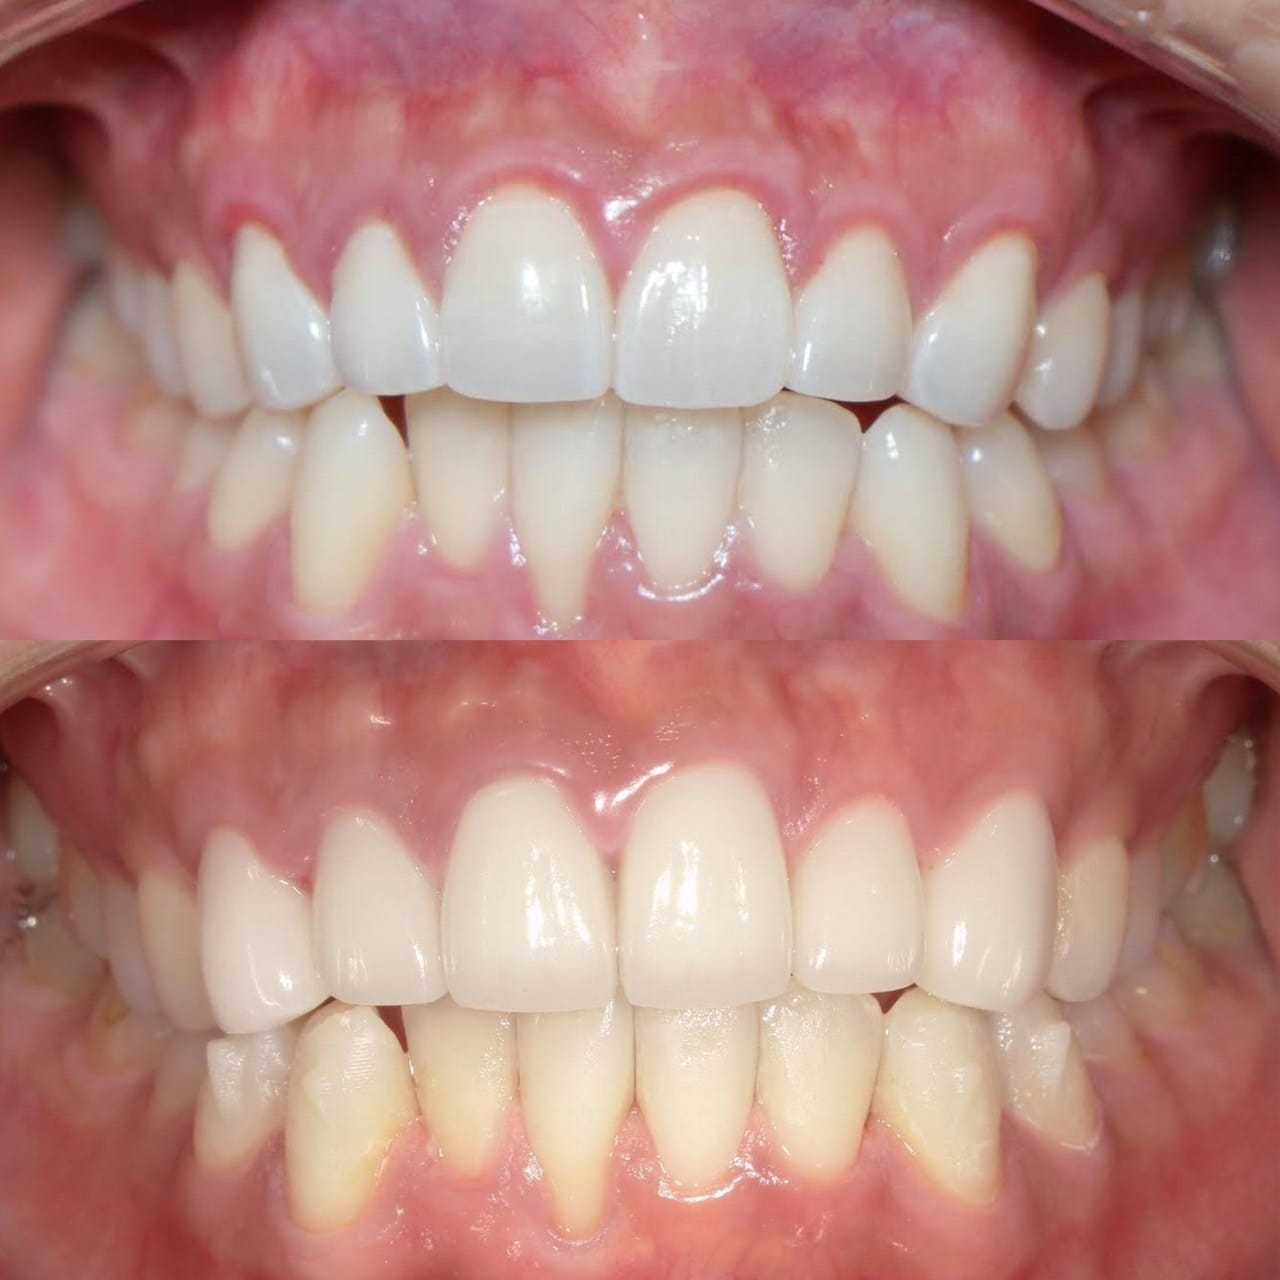

Case022

「歯の長さが短い、歯並びが歪んでる、表面が平面でカッコ悪い、歯茎が腫れている」ということを主訴に来院くださった患者様です。

セラミック矯正は歯科医の技術、センスで仕上がりが全く違うため、審美歯科の中でも担当する歯科医によって最も大きな差の出る診療です。

また、歯並びだけではなく顔貌(お顔立ち)まで綺麗にすることができる診療です。

歯茎の腫れは綺麗に歯を削り直して、正確に型を取り、

精密に作られたセラミックを適合よくセットしてあげることで、前医で入れてから1年以上腫れ続けてた歯茎が1週間で綺麗なピンク色に治りました。

形や並びに関しても、まず歯科医師が「どのような形にするか、どのように並べるか」をイメージしながら綺麗に削ることから始まります。

患者様の主訴通りに綺麗にできて喜んでいただきました。

当院では、患者様の主訴と、治療にかけられる費用、期間によって、ワイヤー矯正、インビザライン、インビザラインGo、セラミック矯正の中から治療法の特徴などをお話しし、その患者様に最適な治療を提案させて頂いております。